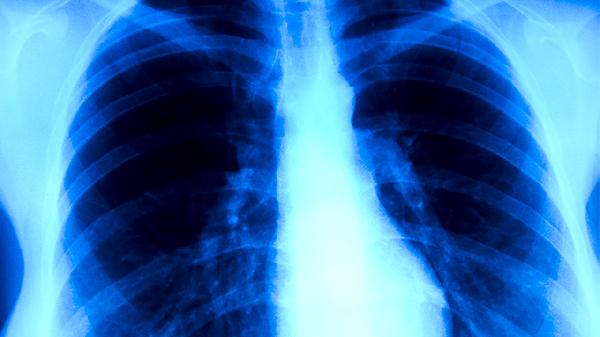

肺心病不會傳染。肺心病是慢性肺源性心臟病的簡稱,屬于非傳染性疾病,其癥狀不會通過接觸、飛沫等途徑傳播給他人。肺心病主要由慢性支氣管炎、肺氣腫等肺部疾病長期發(fā)展導(dǎo)致肺動脈高壓,最終引發(fā)右心室結(jié)構(gòu)和功能改變。

肺心病的典型癥狀包括長期咳嗽、咳痰、活動后氣促、下肢水腫等,這些表現(xiàn)與肺部及心臟功能受損有關(guān)?;颊呖赡艹霈F(xiàn)口唇發(fā)紺、頸靜脈怒張等體征,但均屬于機體病理生理改變,不存在傳染性病原體參與。疾病進展期可合并呼吸衰竭、心力衰竭等嚴重并發(fā)癥,需通過氧療、利尿劑、強心藥物等綜合治療控制病情。